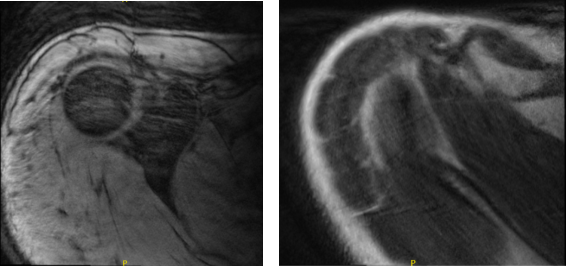

After two weeks post-operative, MRI was presented. Right shoulder MRI showed AC joint sprain and Suspected calcific tendinitis of the supraspinatus tendon.

Repeat X-ray or CT correlation is recommended for definitive assessment. Reviewed the left shoulder MRI, Focal low-grade partial tear of the anterior supraspinatus tendon and mild subacromial subdeltoid bursitis found.

MRI-3T Right Shoulder Non-contrast

MRI-3T Left Shoulder Non-contrast